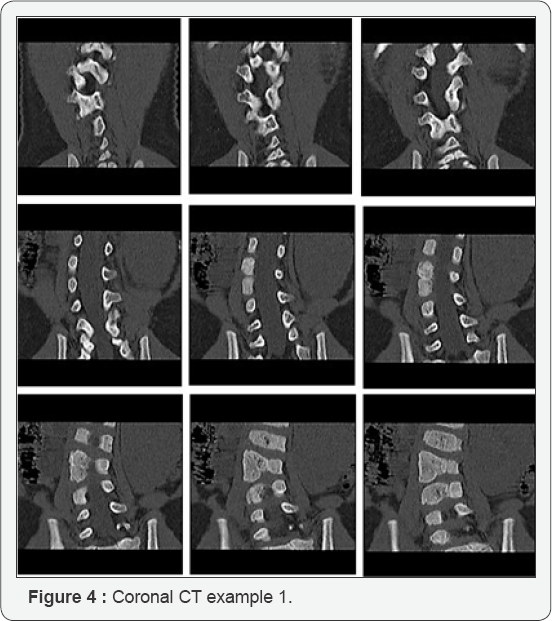

Imaging of sufficient quality to define posterior element anatomy was available in 18 of 24 patients with 1 or more segmented hemivertebrae. Of these 18 patients, 10 had either a spina bifida type lamina or bilamina. The remaining eight patients had 9 hemilamina with an associated hemivertebra demonstrated on coronal CT (7 patients) and coronal MR (1 patient). In 7 of these 9 cases (78%) the hemilamina was found to be one level cranial to the hemivertebrae (Figure 1) and in the remaining 2 cases the hemilamina was at the same level as the hemivertebra (Figure 2). In no case was a hemilamina identified at a level caudal to the associated hemivertebra.

Different techniques including plain radiographs, computed tomography and magnetic resonance imaging, have been used to assess the anatomy of congenital scoliosis. More recently 'Digital Picture Archiving and Communication Systems' (PACS) have become more common. These systems typically allow the viewer to scroll through sequential images in a dynamic manner. This allows for the relationships between structures to be better traced than when comparing images side by side. In this study sequential coronal CT images viewed in this way were found to give the best impression of the relationship between anterior and posterior structures. Alternatively topographical 3D images can be used. However, the precise oblique orientation required to enable the viewer to see both anterior hemivertebra and the posterior hemilamina thus establishing the relationship can be difficult to achieve and often requires the viewer to rotate the 3D image and trace the structures in a similarly dynamic way.